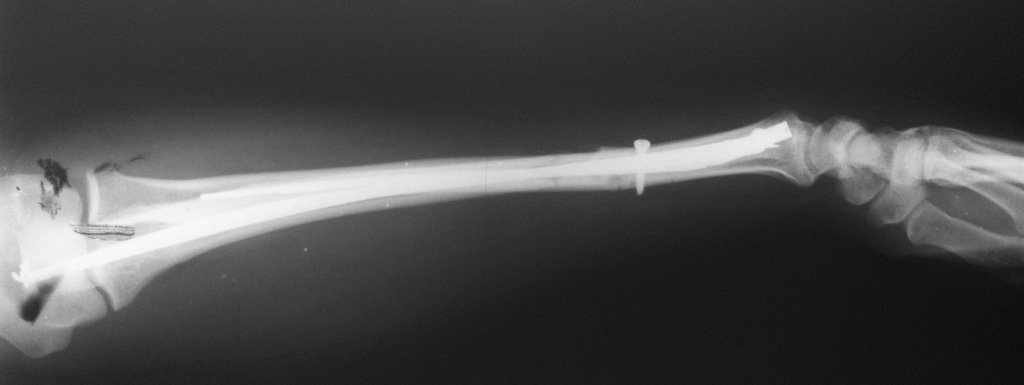

Мы бы выполнили интрамедуллярную фиксацию. Расчет на малоинвазивность при

наличии раны. Даже учитывая деформацию, введение гибкого стержня в radius

через Lister tub. не составит технических сложностей. Правда, наружный

аппарат мы бы наложили из деталей аппарата Илизарова как на рис. 1.

Фиксацию ulna пучком спиц через локтевой отросток. Идея - зафиксировать

малый фрагмент множеством спиц, тем самым исключив подвижность. Канал

видимо широкий, можно провести 4-5-6 спиц. "Ёжик", думаю удержит даже

порозный отломок.

> Уважаемые коллеги. Пациентка 82 лет, "сохранного вида" получила

> вторичнооткрытый перелом костей левого предплечья. Рана по передней

> поверхности, в области головки локтевой кости.

> Около 20-ти лет назад был перелом лучевой кости в типичном месте, который

> сросся с тыльным смещением.В ургентном порядке наложен АВФ. Рана заживает

> первичным натяжением. Визуально предплечье ровное. Можно ли оставить так

> как есть?